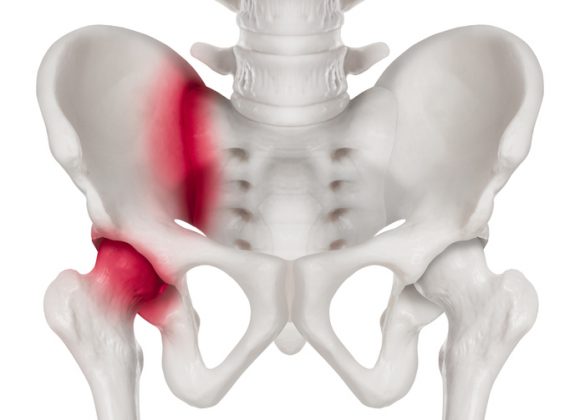

7. 고관절 충돌증후군

대퇴골두와 비구가 반복적으로 맞닿아 충돌하면서 통증이 생기는 상태입니다. 양반다리나 다리를 넓게 벌리는 동작에서 통증이나 저림이 느껴진다면 의심해 볼 수 있습니다. 방치하면 비구연골이 손상되어 퇴행성 관절염으로 이어질 수 있으므로 주의가 필요합니다.